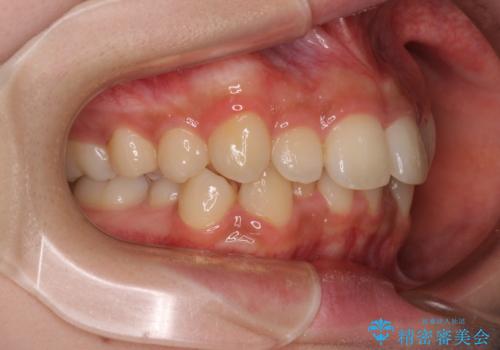

- 上顎前歯の突出感を気にして来院された患者様です。

上下左右第一小臼歯4本を抜歯して、積極的に口元を引っ込めるよう、ワイヤー装置にて矯正治療を行うこととしました。